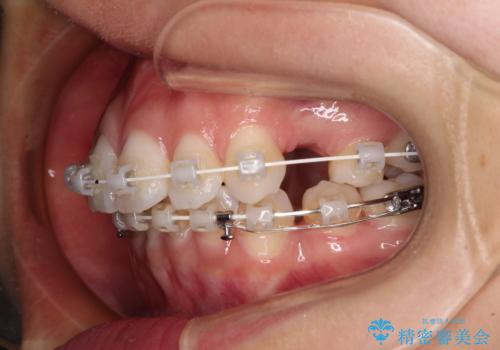

補助装置を用いて上顎歯列全体を後方に移動させ、下顎は左右で抜歯する小臼歯を変えることで、左右の咬み合わせをより理想的な位置となるように計画しました。

埋伏している右下第二大臼歯は、牽引して咬合に参加させることで計画しましたが、癒着などにより移動困難な場合には、抜歯の上インプラント補綴治療を行うこととしました。